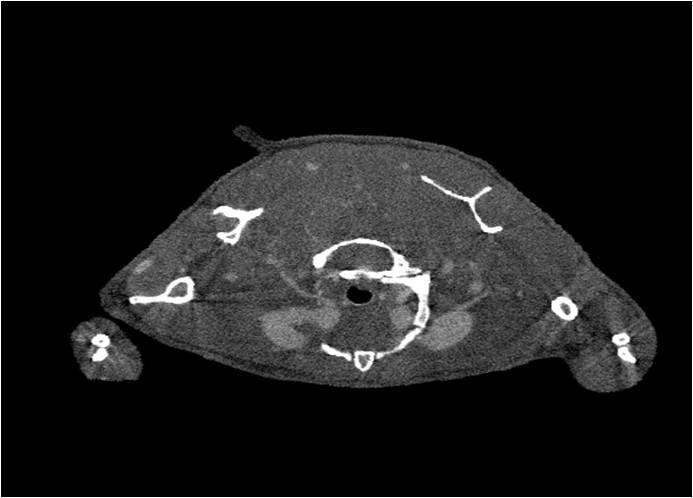

心血管

胸部和心血管的層析成像 胸部和心血管的3D圖像